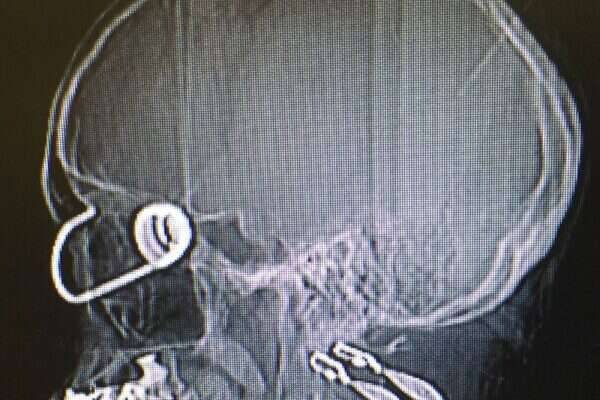

בעקבות המקרה, הדגיש פרופ׳ לייבוביץ': "הוו שמחובר לגומי (בנג׳י קורד) הינו סוגר מסוכן מאוד שכבר גרם למקרים של פגיעה עינית עד כדי עיוורון. אני מבקש להזהיר וליידע את הציבור שעדיף להימנע משימוש בו״.